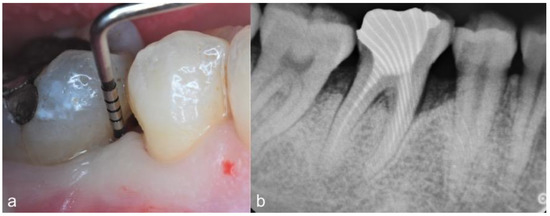

2. Case Series

2.2. Clinical Findings

2.4. Follow-Up and Outcomes